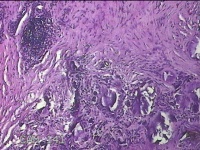

左外踝包块

性别

男

年龄

31岁

临床诊断

皮下结节

一般病史

发现左外踝包块1年余。

标本名称

大体所见

灰白暗红色包块1.8x1.3x0.7cm一个,表面糜烂,切开包块,内见大量石灰样物,内壁粗糙。

去了解病史,应该是痛风结节。